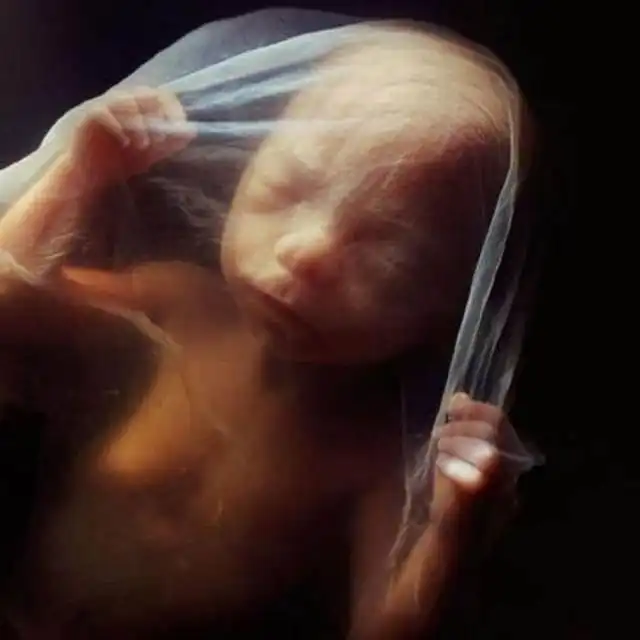

16 недель. Любознательный малыш уже использует свои руки для изучения окрестностей.

Скелет в основном состоит из гибкого стержня и сети кровеносных сосудов, видимой сквозь тонкую кожу.